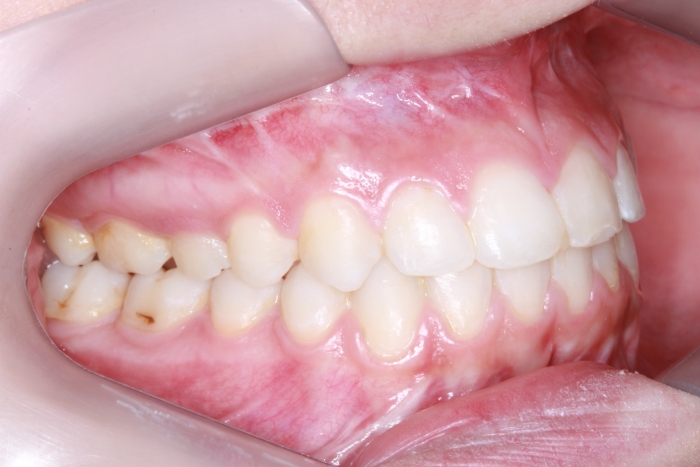

Mordida inicial

Oclusão após a cirurgia